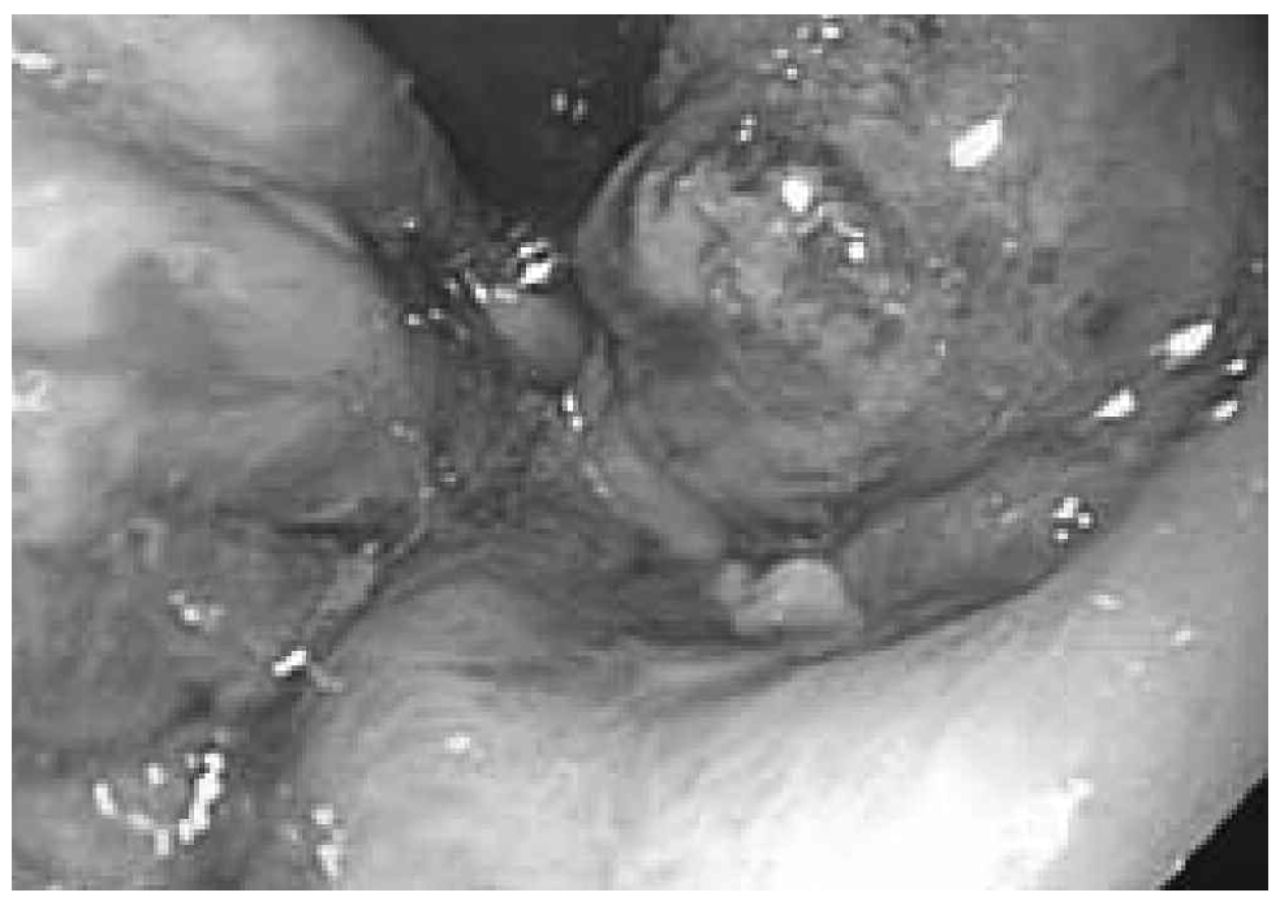

Patients with systemic AL amyloidosis were offered anti-plasma cell chemotherapy. HDM/SCT was offered as first-line therapy, as we and others have observed a high rate of hematologic complete responses and durable remissions in patients who achieve a complete response; we found an overall 6.3-year median survival and 43% complete response rate in our recent update.19 However, patients with GI amyloidosis and evidence of active GI bleeding or ulceration were not offered myeloablative chemotherapy, because of the risk of catastrophic GI hemorrhage (Figures 3 and 4).20 In the series we report here, severe GI bleeding occurred in only 6% of patients treated with HDM/SCT, which is comparable to rates of GI hemorrhage in other reported transplant series.21,22 None of our selected patients died due to GI bleeding. Patients who were not candidates for HDM/SCT were treated in clinical trials with novel agents or with melphalan and dexamethasone.

Figure 3.Endoscopic appearance of gastric ulceration in a patient with AL amyloidosis and severe gastrointestinal hemorrhage.

Figure 4.Endoscopic appearance of gastric submucosal hematoma in a patient with AL amyloidosis and severe gastrointestinal hemorrhage.